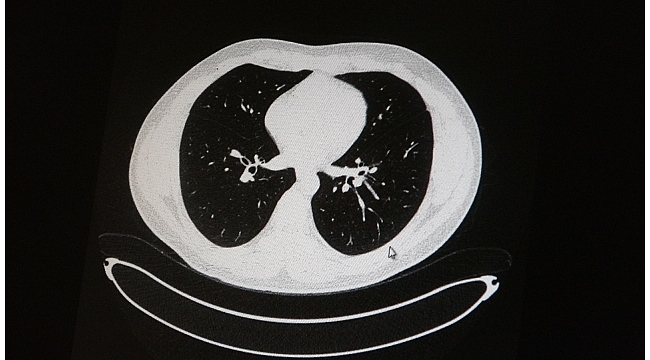

Elazığ'da öksürük, halsizlik, yorgunluk ve çabuk yorulma gibi şikayetlerle hastaneye başvuran ve korona virüs tespit edilen 2 genç hastadan aşısız olanının tomografi sonuçlarında virüsün akciğerlerde zatürreye sebebiyet verdiği görüldü. Aynı şekilde aşı olup korona virüs hastalığına yakalanan bir başka genç hastanın bilgisayarlı akciğer tomografisinde akciğerinde herhangi bir sorunun olmadığı belirlendi.

Medical Park Elazığ Hastanesi Göğüs Hastalıkları Uzmanı Dr. Cebrail Azar, geçtiğimiz yıla oranla yoğun bakımda yatan hastaların yaş ortalamasının 65'ten 35'lere kadar düştüğüne dikkat çekti. Genç olduğu halde aşı olmayanlarda hastalığın ağır seyrettiğini ifade eden Uzm. Dr. Azar, "Ben gencim, benim bağışıklık sistemim kuvvetli" diyen genç bir hastanın akciğerlerinde ciddi lekelenmelerin olduğunu ve korona virüs zatürresi olduğunu gördüklerini belitti. Uzm. Dr. Azar, aynı şekilde aşı olup korona virüs hastalığına yakalanan bir başka genç hastanın akciğer tomografisinde akciğerde herhangi bir sorunun olmadığını ve hastanın durumunun iyi olduğunu gözlemlediklerini kaydetti. Uzm. Dr. Azar, sürekli şahit oldukları "Keşke biz aşı olsaydık" sözünü bir daha duymamak için herkesi aşı olmaya davet etti.